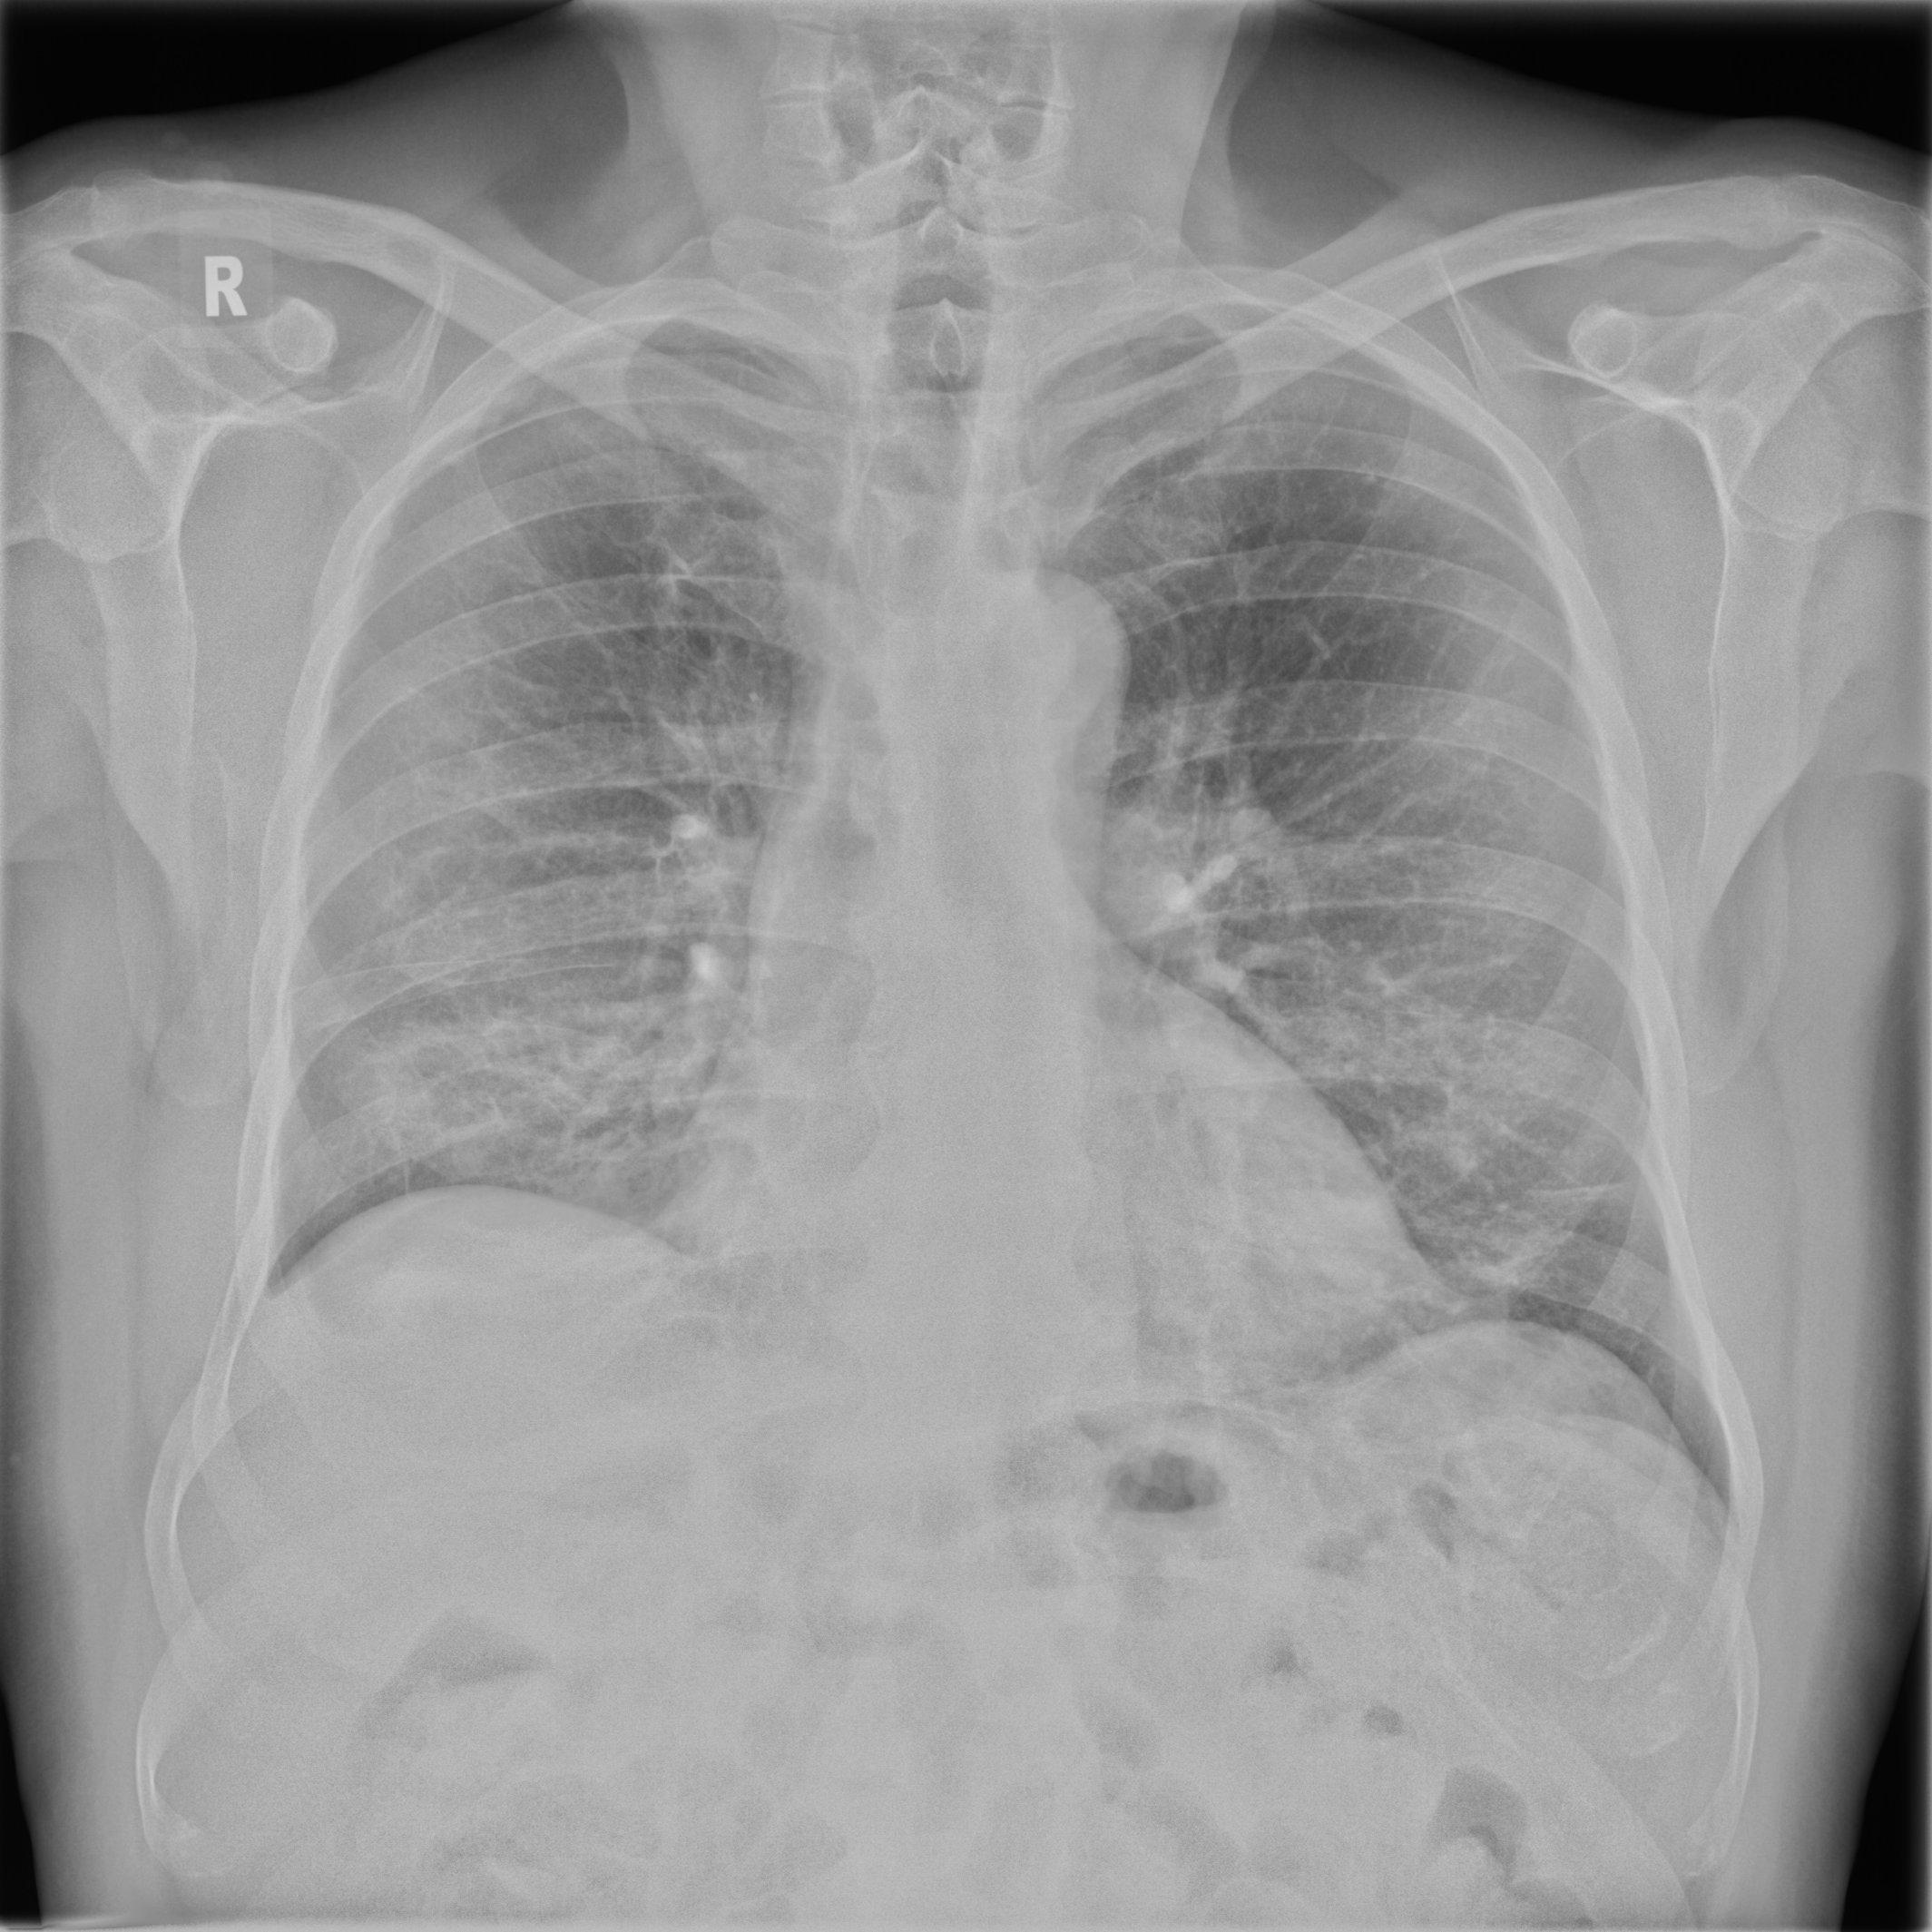

3.3.2 Data

Posteroanterior chest radiographs were acquired on two imaging systems (both Discovery XR656 HD models, GE Healthcare, USA) at Cambridge University Hospitals NHS Trust. Each scanner was being set up in the hospital with different post-processing parameters (chosen by the operating radiologists), which are used here as reference images, see Figure 7 and 8(a). Additional images, serving as real-life examples of lower quality, were produced for each radiographic exposure using multiple different post-processing settings. The post-processing was applied in the hospital directly on the scanner itself by adjusting parameters in the provided framework.

Refer to caption

(a) Reference

(b) (21.1, 0.90, 0.11)

(c) (19.5, 0.88, 0.16)

Figure 7: Chest X-Ray scans with different kinds of post-processing; (a) serves as reference and (b) is wrongly judged as better visualization by PSNR/SSIM/LPIPS.

(b) (22.8, 0.97, 0.08)

(c) (21.2, 0.96, 0.07)

Figure 8: Chest X-Ray scans with different kinds of post-processing; (a) serves as reference, (b) is wrongly judged as better visualization by PSNR and SSIM, LPIPS gives a slightly worse evaluation for (b).

FR-IQA mismatches

In Figure 7, contrast deviation and edge enhancement were reduced in (b), but increased in (c), the noise reduction algorithm was removed in both. The brightness was increased in both images but more so in (c) and low-contrast enhancement was removed in (b). The result is that (b) has relatively low contrast in the lungs compared to the reference (a) and radiograph (c). In Figure 8, edge enhancement has been dramatically increased in (b), whilst the contrast deviation and tissue contrast have been reduced. In (c), the brightness, tissue contrast and edge enhancement have been slightly increased. Consequently, (b) provides low contrast in the lungs with excessively prominent lung markings and vasculature which make it harder to detect abnormalities such as a pneumonia.

All of the chosen FR-IQA metrics wrongly judge (b) as the better image in the first example Figure 7, and the results in (b) and (c) of the second example Figure 8 are quite close, where PSNR and SSIM are also providing the wrong order. The tested measures are not suitable to evaluate the quality of data sets with X-Ray images that have large variations regarding contrast, luminance and sharpness.